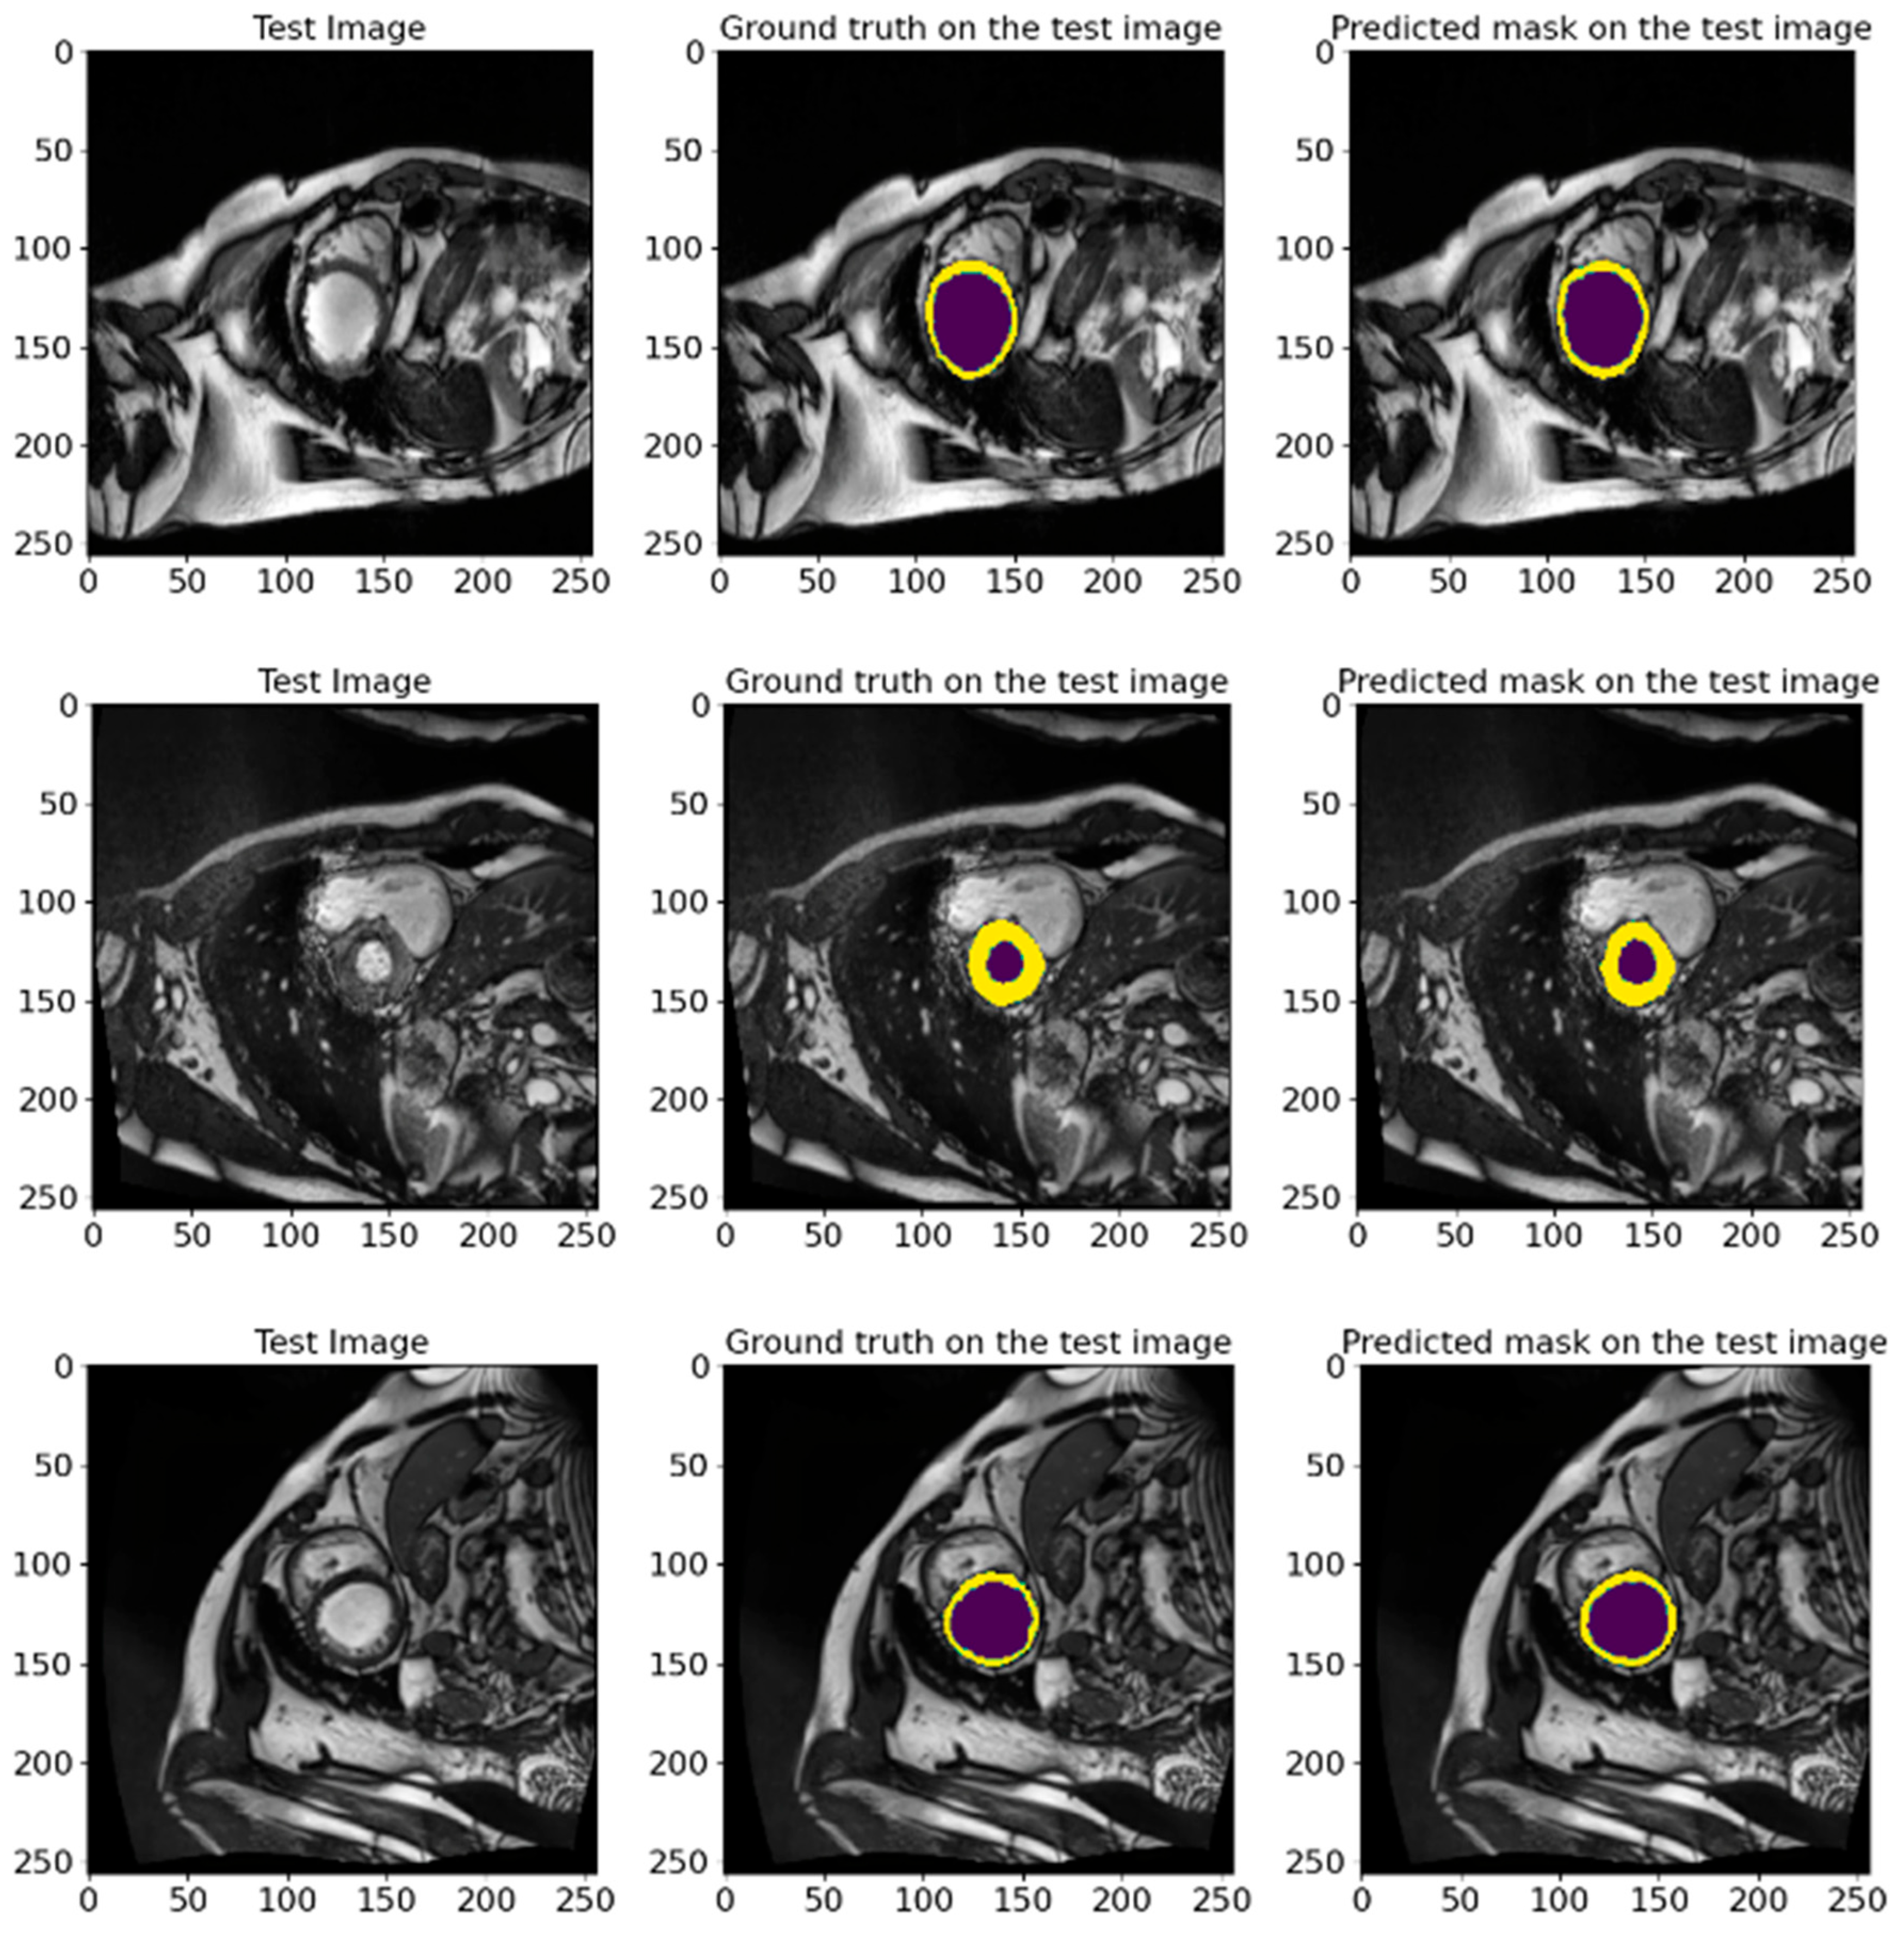

Figure 9 illustrates various examples from the test dataset with the corresponding actual masks generated by the experts and the predicted masks produced by our model. Examples demonstrate the segmentation accuracy of the model. A comparison of the actual and predicted masks shows that the proposed model successfully identifies the significant structures of the cardiac region, including the left ventricle and myocardium. The model demonstrates a high accuracy even in complex cases where the boundaries of the structures are less clear. These visual results confirm the effectiveness of the developed pre-processing methods and model architecture in improving the quality of the automatic segmentation of medical images. Our proposed heart segmentation model based on deep neural networks and image enhancement demonstrated a high efficiency and accuracy. It confirms its potential for use in clinical practice and contributes to improving methods for diagnosing cardiovascular diseases.

Figure 9.

Representative examples from the EMIDEC test set, showing the GT masks and the corresponding predictions made by our model. The deep violet areas represent the LV, while the yellow areas correspond to the Myo.